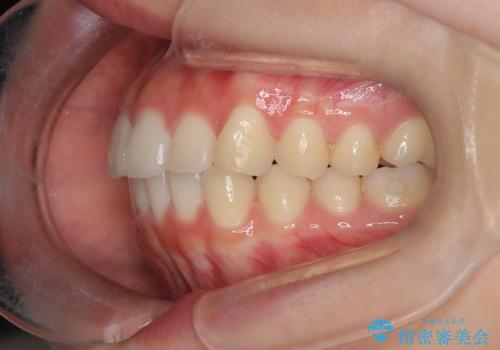

【インビザライン】前歯を下げたい

- 前歯が出ていることを主訴に来院されました。

奥歯を後ろに動かしながらスペースを作ることで、前歯を下げることができ患者さんにも満足していただきました。

治療中に顎間ゴムを使用していただいたおかげで、スムーズに治療を行うことができました。